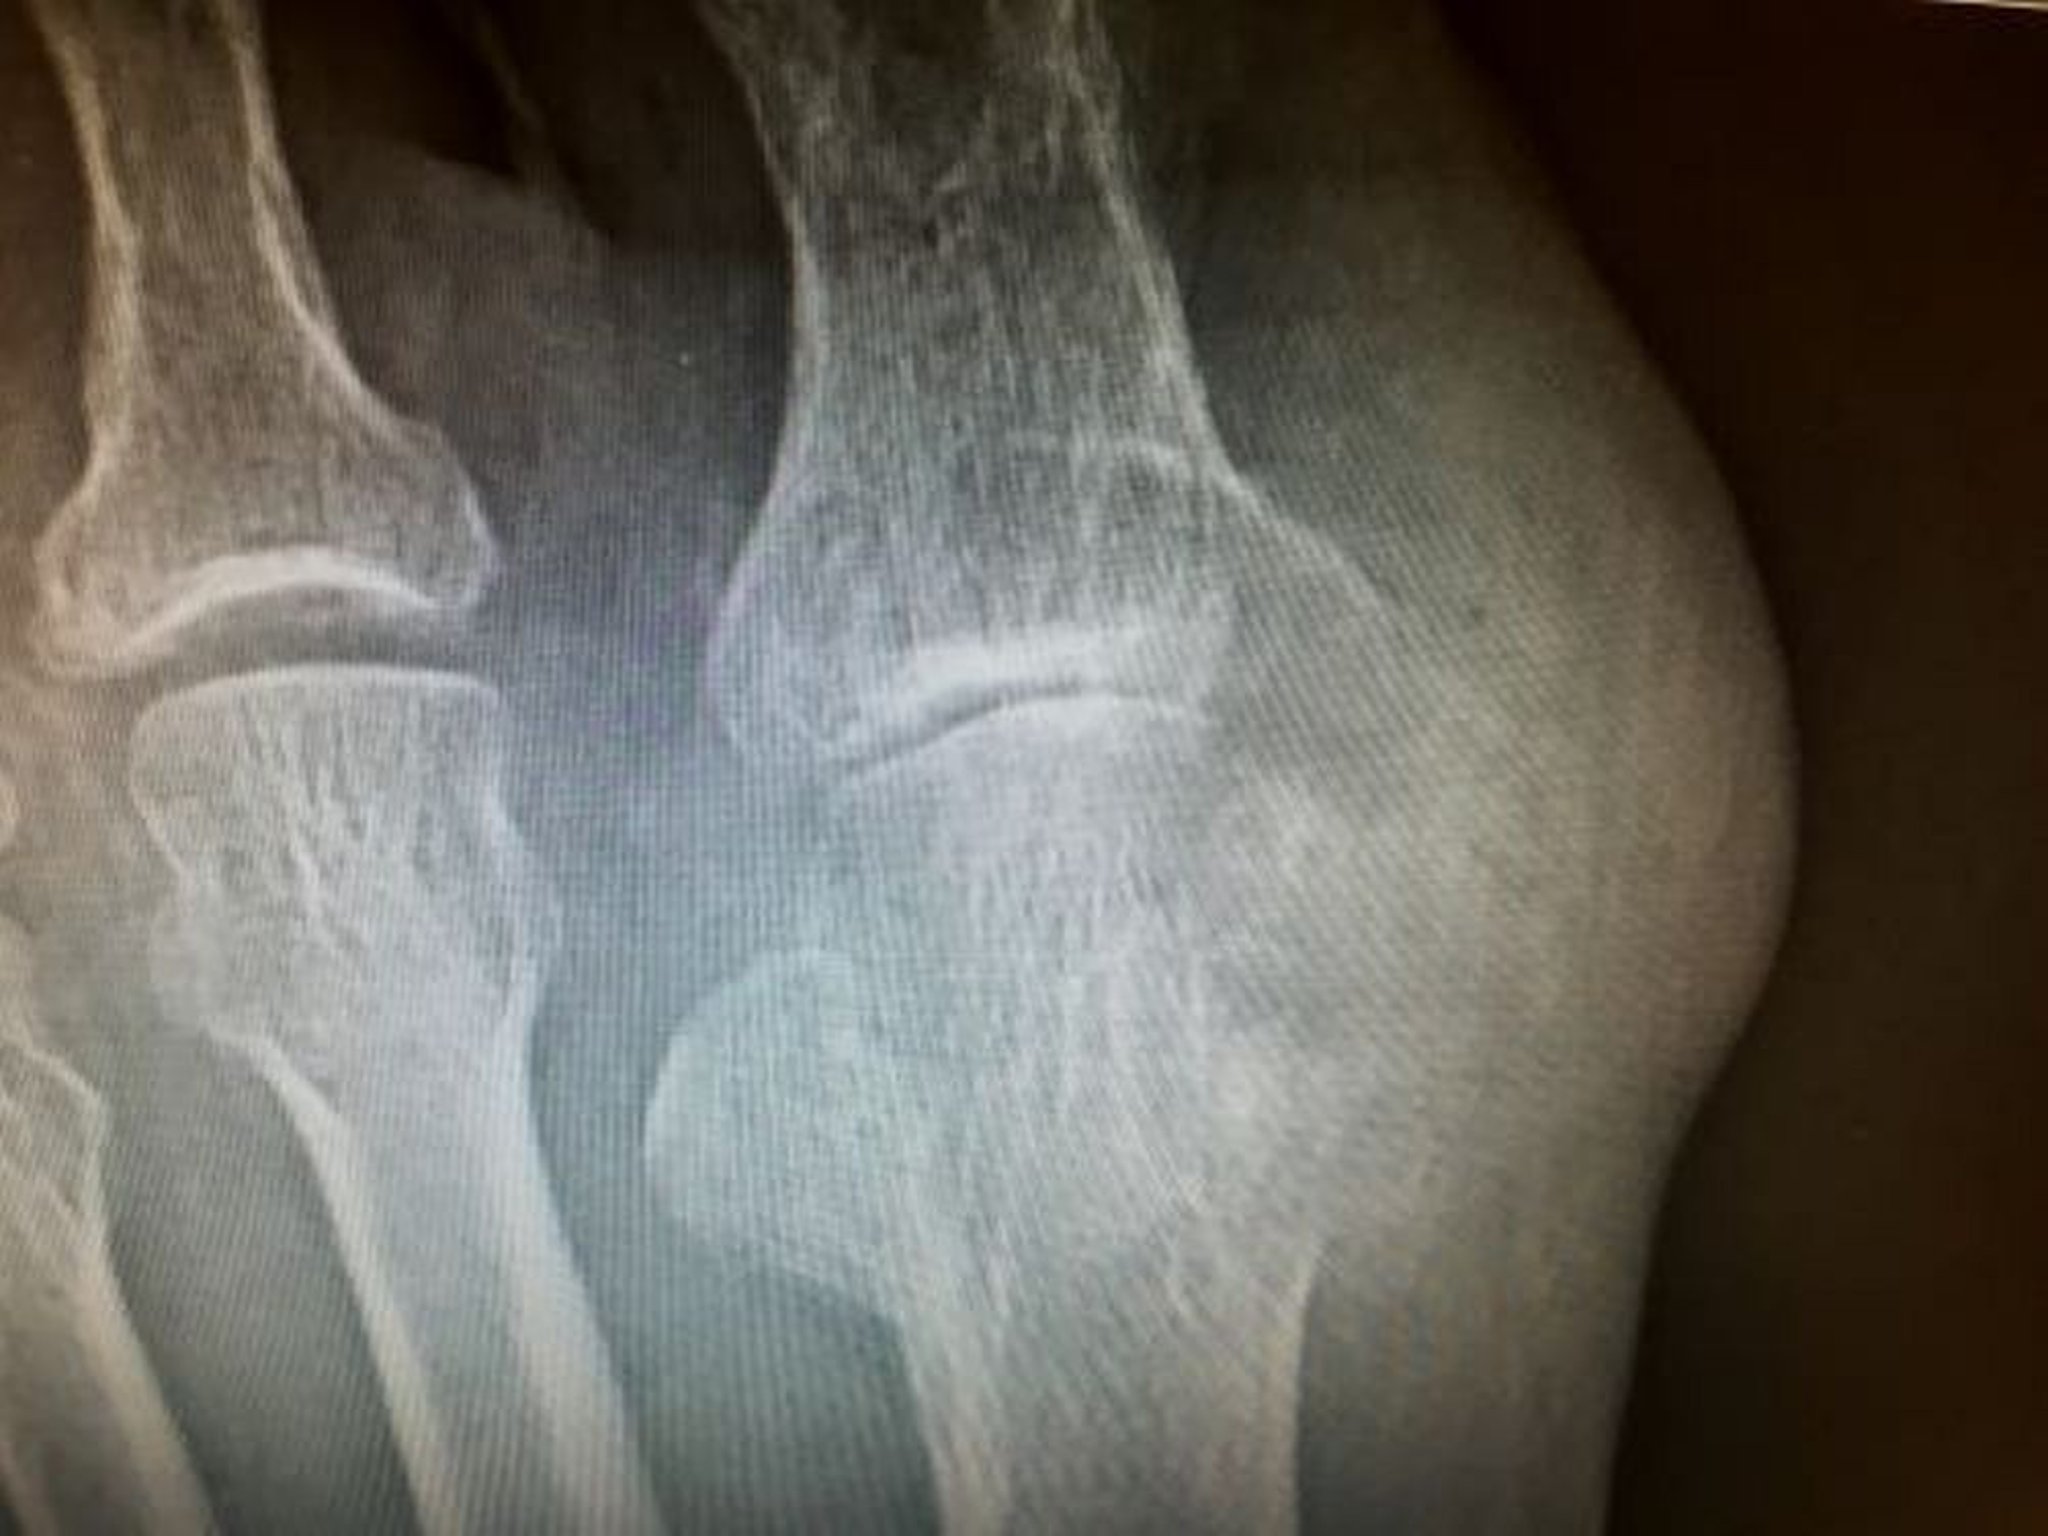

Tofo con erosione

Questa foto mostra grandi erosioni provocate da tofi che coinvolgono il metatarso distale e la falange prossimale del dito grosso.

Image courtesy of N. Lawrence Edwards, MD.